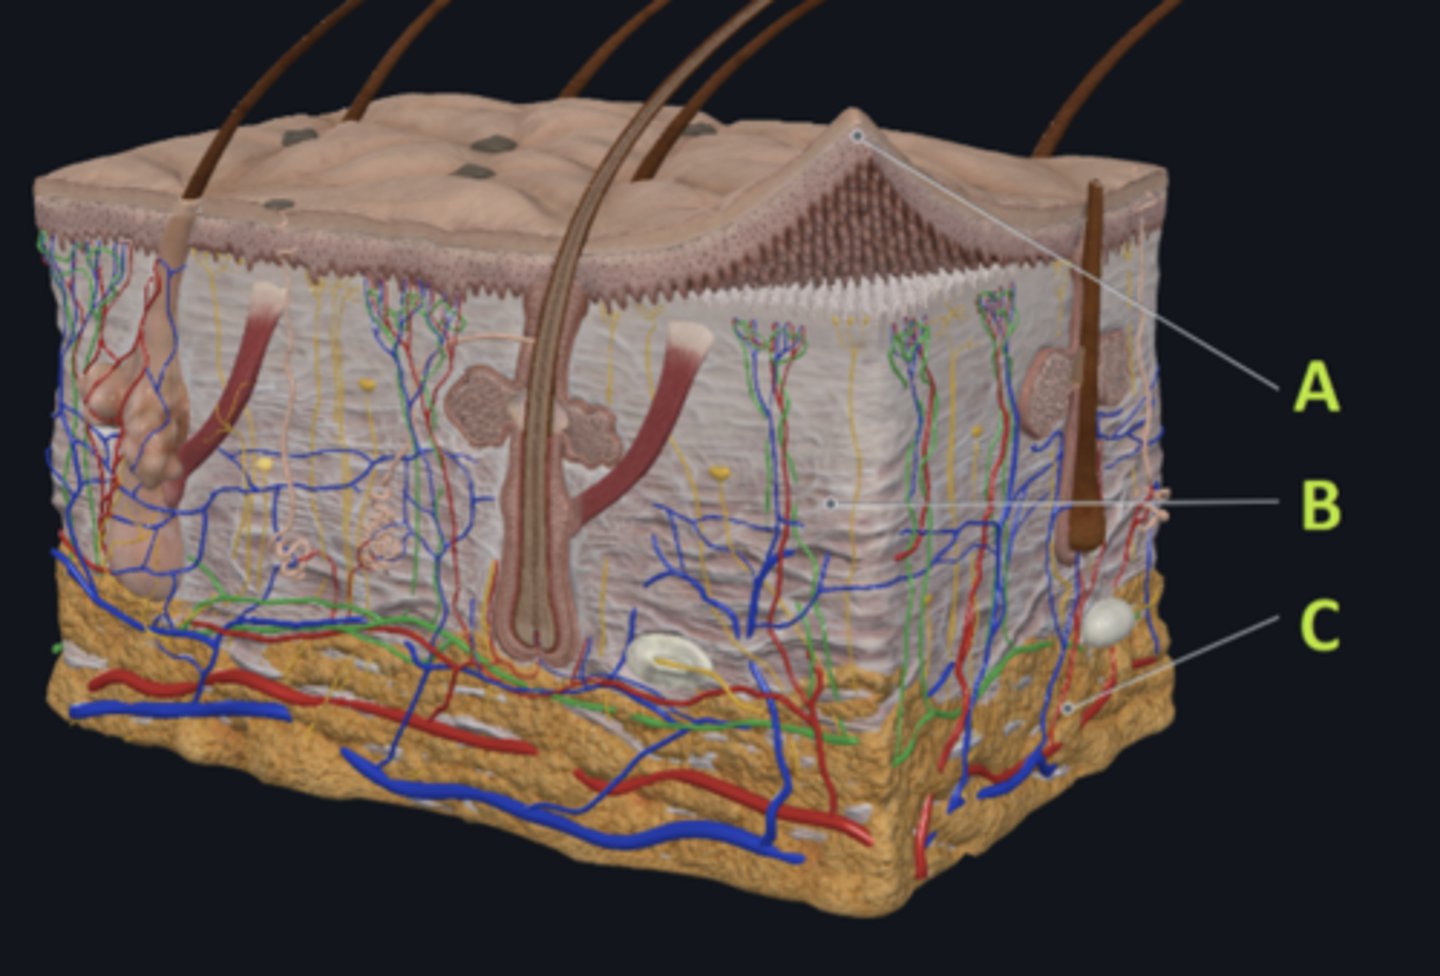

C - hypodermis

Answer the following questions based on the features indicated in the following image. Which letter indicates the administration site for subcutaneous injections?

A - epidermis

Answer the following questions based on the features indicated in the following image. Which letter indicates the administration site for topical creams and ointments?

B - Dermis

Answer the following questions based on the features indicated in the following image. Which letter indicates the administration site for the tuberculin skin test?

A - epidermis

Answer the following questions based on the features indicated in the following image. Which letter indicates a region of the skin with no nerves or blood vessels?

B - Dermis

Answer the following questions based on the features indicated in the following image. Which letter indicates the region where skin appendages (sweat glands, sebaceous glands, and hair follicles) have their roots?

Epithelial tissue

Answer the following questions based on the features indicated in the following image. Which of the four major tissue types is indicated by letter A?

Which letter indicates the administration site for insulin injections?

A

Which letter indicates the administration site for a lidocaine patch?

B

Which letter indicates the administration site for an allergy test?

B

Which letter indicates a region of the skin rich in dense, irregular connective tissue?

C

Which letter indicates the region most important for energy storage and thermal insulation?

Connective

Which of the four major tissue types is indicated by letter C?